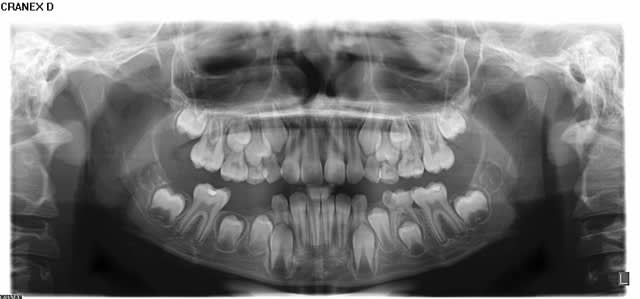

Au niveau dentaire, on observe un taurodontisme (voir molaires sur panoramique).

Il faut regarder les 6 du haut, surtout la 26. En bas, les dents sont nécrosées, le développement s'est arrêté.

L'enfant a 9 ans : compare les molaires du haut avec les pano d'enfants du même age ci-dessous.